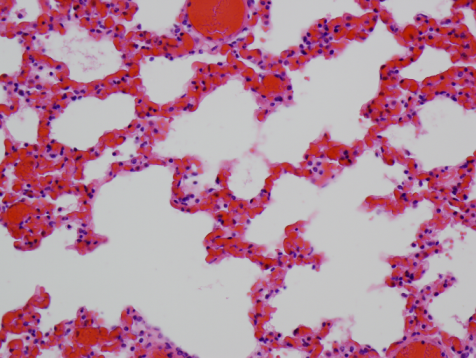

In this section, we present the experimental results of applying DFDL to three diverse histopathological image databases (sample images are shown in Fig. 2.) and compare our results with those using SVM in conjunction with a collection of state-of-the-art histopathology features from WND-CHARM[7] (will be referred as WND-CHARM method), SRC [11], LA-SHIRC [3] and other DL methods (LC-KSVD [20] and FDDL [21]). In each experiment, 10000 20-by-20 patches are randomly extracted from training images for each class. Each Dictionary Learning method learns the same number of bases, say 500, per class.

Refer to caption

(a) UDH

(b) Healthy Lung

(c) Not MVP

(d) DCIS

(e) Inflamed Lung

(f) MVP

Fig. 2: Samples from three data sets. Column 1: IBL data set, column 2: ADL data set, column 3: TCGA data set

ADL-Lung data set: This database contains bovine histopathology images of lung acquired by pathologists at the Animal Diagnostics Lab, Pennsylvania State University. These images are scanned using a whole slide digital scanner at 40x optical magnification and are of size 4000×3000400030004000\times 3000 pixels. For the purpose of computational speed-up, all images are downsampled to 400×300400300400\times 300 pixels in an aliasing-free manner. This database consists of images from two classes: healthy and inflammatory. Each class has 150 images from which 40 images are chosen for training, the remaining ones are used for testing. The averaging experiment results over 10 trials for different methods are presented in Table 1. Apparently, SHIRC and LC-KSVD are moderately suitable to detect inflammatory while WND-CHARM only provides a fairly high-performance in recognizing healthy organs. In contrast, DFDL offers the best accuracy in both detecting Healthy and Inflamed organs with more than 92 percent in the former and over 94 percent in the latter.